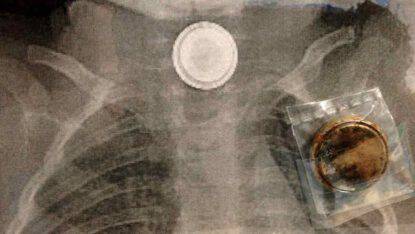

Ingerire queste pile può essere molto dannoso per la salute del bambino spiega il Dottore Paolo Gandullia direttore dell’UOC Gastroenterologia del Gaslini: “Nei 4 casi di ingestione di pila a bottone, la risposta dei genitori è avvenuta in tempi diversi e con prognosi potenziale molto diversa. In uno dei casi la bimba era stata portata dai genitori presso uno dei Pronto Soccorso della Regione, trascorsi diversi giorni dall’ingestione della pila, in seguito all’evacuazione della pila insieme a feci nere, segno di sanguinamento digestivo alto (esofago, stomaco e duodeno). In questo caso ha funzionato molto bene la collaborazione tra le strutture del territorio ed il Gaslini: è stato applicato il protocollo condiviso e consolidato a livello italiano ed internazionale, che prevede l’invio del bambino all’hub pediatrico e l’attivazione immediata di tutti gli specialisti: radiologo, cardiochirurgo e anestesista, gastroenterologo mentre il bambino è ancora in viaggio, per pianificare immediatamente dopo l’arrivo in Pronto Soccorso tutte le misure da prendere, in un ambito clinico, dove è vitale essere tempestivi. Il protocollo prevede, tra le altre cose, di sottoporre il bambino ad una immediata angiografia TC con contrasto, per valutare la presenza della complicanza più temibile dell’ingestione di una pila a bottone, rappresentata dalla fistola aorto-esofagea“.

La Dotteressa Emanuela Piccotti, direttore del Pronto Soccorso del Gaslini. ci mette in gurada su questi piccoli corpi estranei e dove si possono trovare: “L’ingestione di corpi estranei nel bambino piccolo rappresenta un pericolo reale e un frequente motivo di accesso al Pronto Soccorso. Esistono corpi estranei particolarmente pericolosi e dannosi per le strutture interne dell’organismo: in particolare le pile a bottone, alcaline o al litio. Si tratta di dischi metallici delle dimensioni di un bottone o di una piccola moneta che si trovano nei giocattoli, oltre che in una serie di strumenti di uso quotidiano come orologi, sveglie, apparecchi acustici, telecomandi, etc…L’ingestione di una pila a bottone, specie se avviene lontano dagli occhi di chi accudisce i bambini, può provocare sanguinamenti intestinali, dolore toracico o dorsale, improvviso rifiuto del cibo, vomito, scialorrea, tosse e sintomi respiratori”.